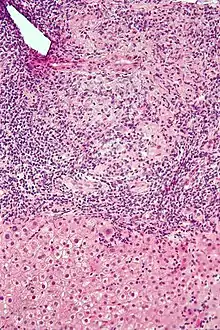

Micrograph of PBC showing bile duct inflammation and injury, H&E stain

On microscopic examination of liver biopsy specimens, PBC is characterized by chronic, nonsuppurative inflammation, which surrounds and destroys interlobular and septal bile ducts. These histopathologic findings in primary biliary cholangitis include:[32]

• Inflammation of the bile ducts, characterized by intraepithelial lymphocytes

• Periductal epithelioid granulomas.

• Proliferation of bile ductules

• Fibrosis (scarring)

The Ludwig and Scheuer scoring systems have historically been used to stratify four stages of PBC, with stage 4 indicating the presence of cirrhosis. In the new system of Nakanuma, the stage of disease is based on fibrosis, bile duct loss, and features of cholestasis, i.e. deposition of orcein-positive granules, whereas the grade of necroinflammatory activity is based on cholangitis and interface hepatitis. The accumulation of orcein-positive granules occurs evenly across the PBC liver, which means that staging using the Nakanuma system is more reliable regarding sampling variability.